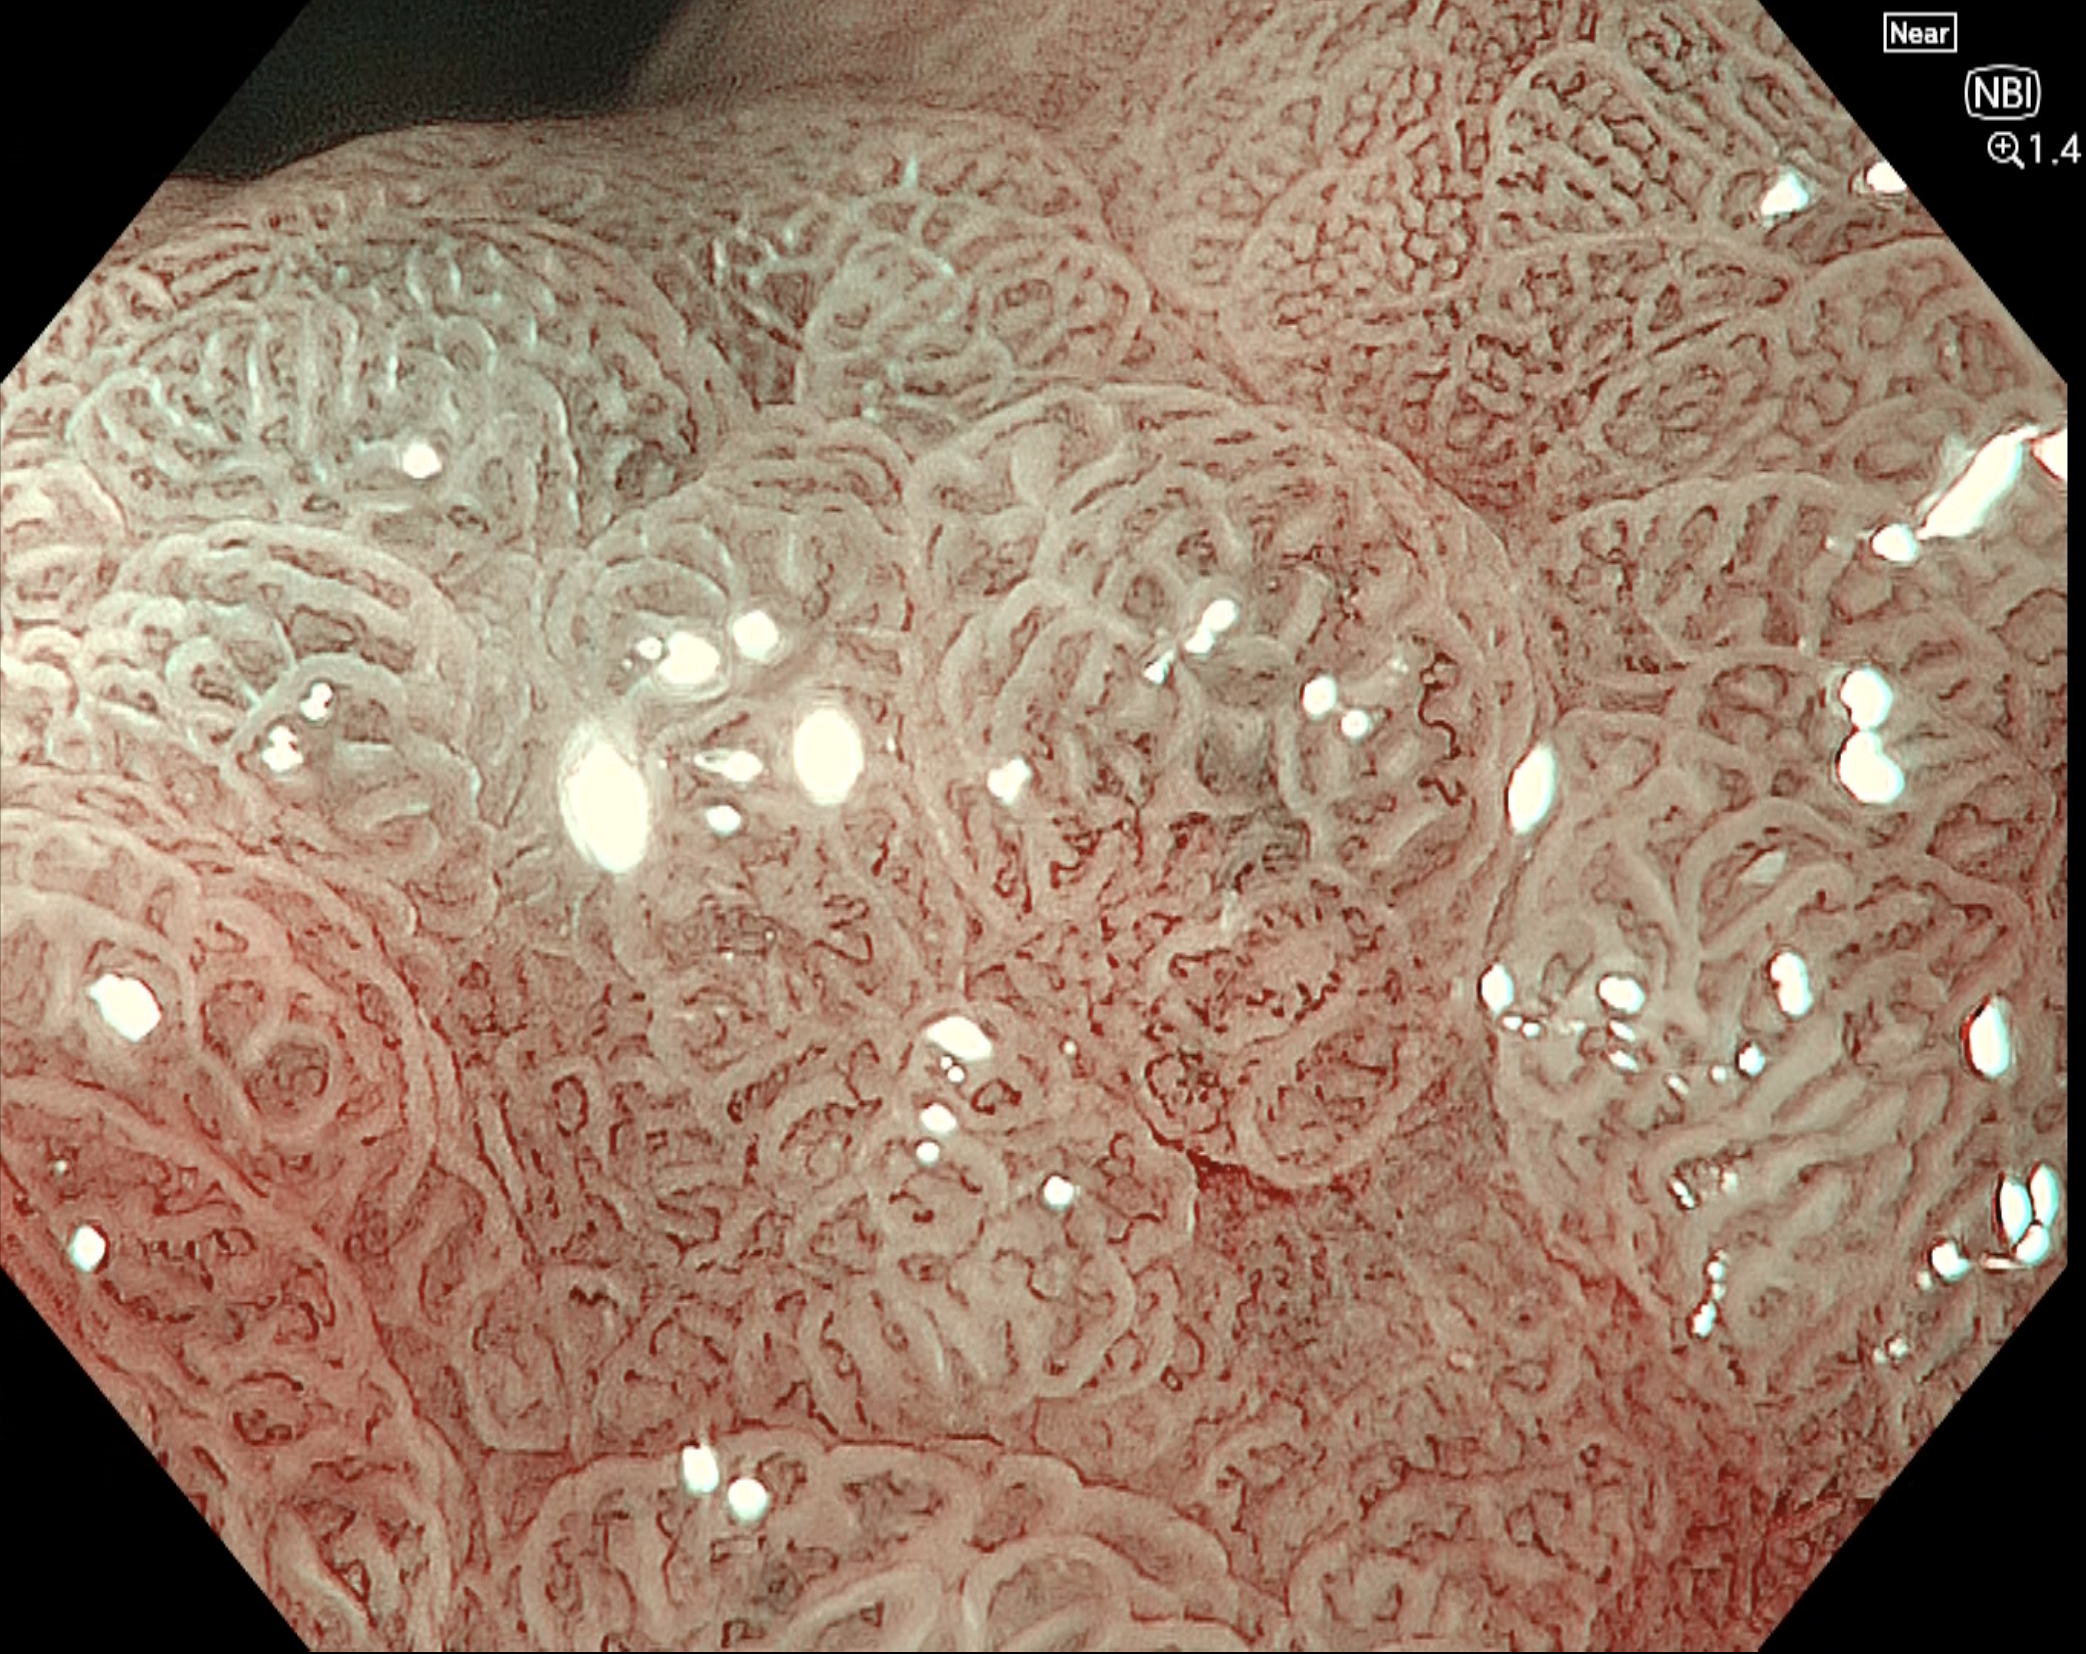

• NBI観察(電子拡大)

強調設定:B8

図8

腫瘍口側におけるNBI併用拡大画像(near focus+電子拡大1.4倍)を提示する。